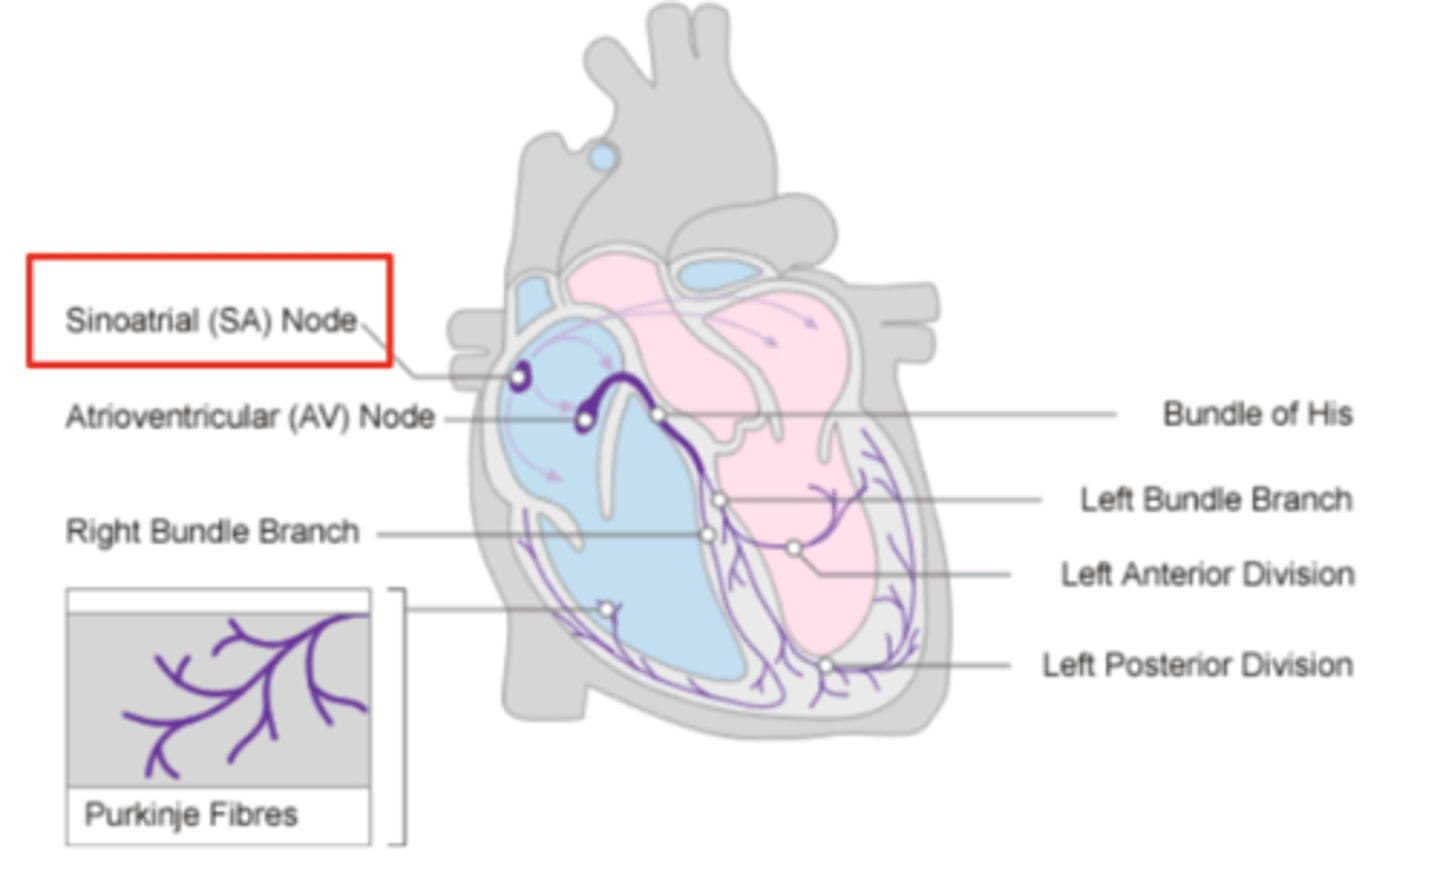

What allows the heart to contract by itself?

The heart possesses a specialized conduction system that gives it the autonomous capacity to contract, allowing it to pump by itself in a correct buffer.

What are the two conduction nodes of the heart conduction system?

. SA node (sinoatrial node)

. AV node (atrioventicular node)

What is the function of the sinoatrial (SA) node?

Pacemaker of the heart

Where is initiated the contraction of the SA node?

SVC (Superior Vena Cava)

passing through the atrium to the AV node

Where is the SA located?

upper wall of the right atrium,

at the junction where the superior vena cava enters

Where is the atrioventricular (AV) node located, and what follows it?

At the level of the atrioventricular septum,

AV node is followed by?

Bundle of Hiss that divides into two branches

Where does Bundle of Hiss ends?

Purkninje fibers

Describe the propagation of waves in the conduction system ?

. SA node sends the initial wave

Passes through the walls of the atria

. Ends at the AV node in the AV septum

. Travels along the Bundle of His

. Reaches Purkinje fibers in the walls of the ventricles

What role does the moderator band play in the conduction system?

Allows the wave to reach the papillary muscles, inducing their contraction simultaneously with that of the ventricles.

REMEMBER: PAPILLARY MUSCLES ACT THROUGH THE CHORDAE TENDINAE TO CONTROL THE TRICUSPID AND MITRAL VALVES.

What is the significance of the Bundle of His in heart conduction?

Branching to the right and left to ensure coordinated contraction of the ventricles.

What are the Purkinje fibers, and what is their function?

specialized conductive fibers in the walls of the ventricles that

facilitate rapid transmission of electrical impulses,

ensuring efficient and synchronized ventricular contraction.

How does the AV node contribute to heart rhythm?

Delays the electrical impulse from the SA node,

ensuring that the atria contract fully to transfer blood to the

ventricles before the ventricles contract.